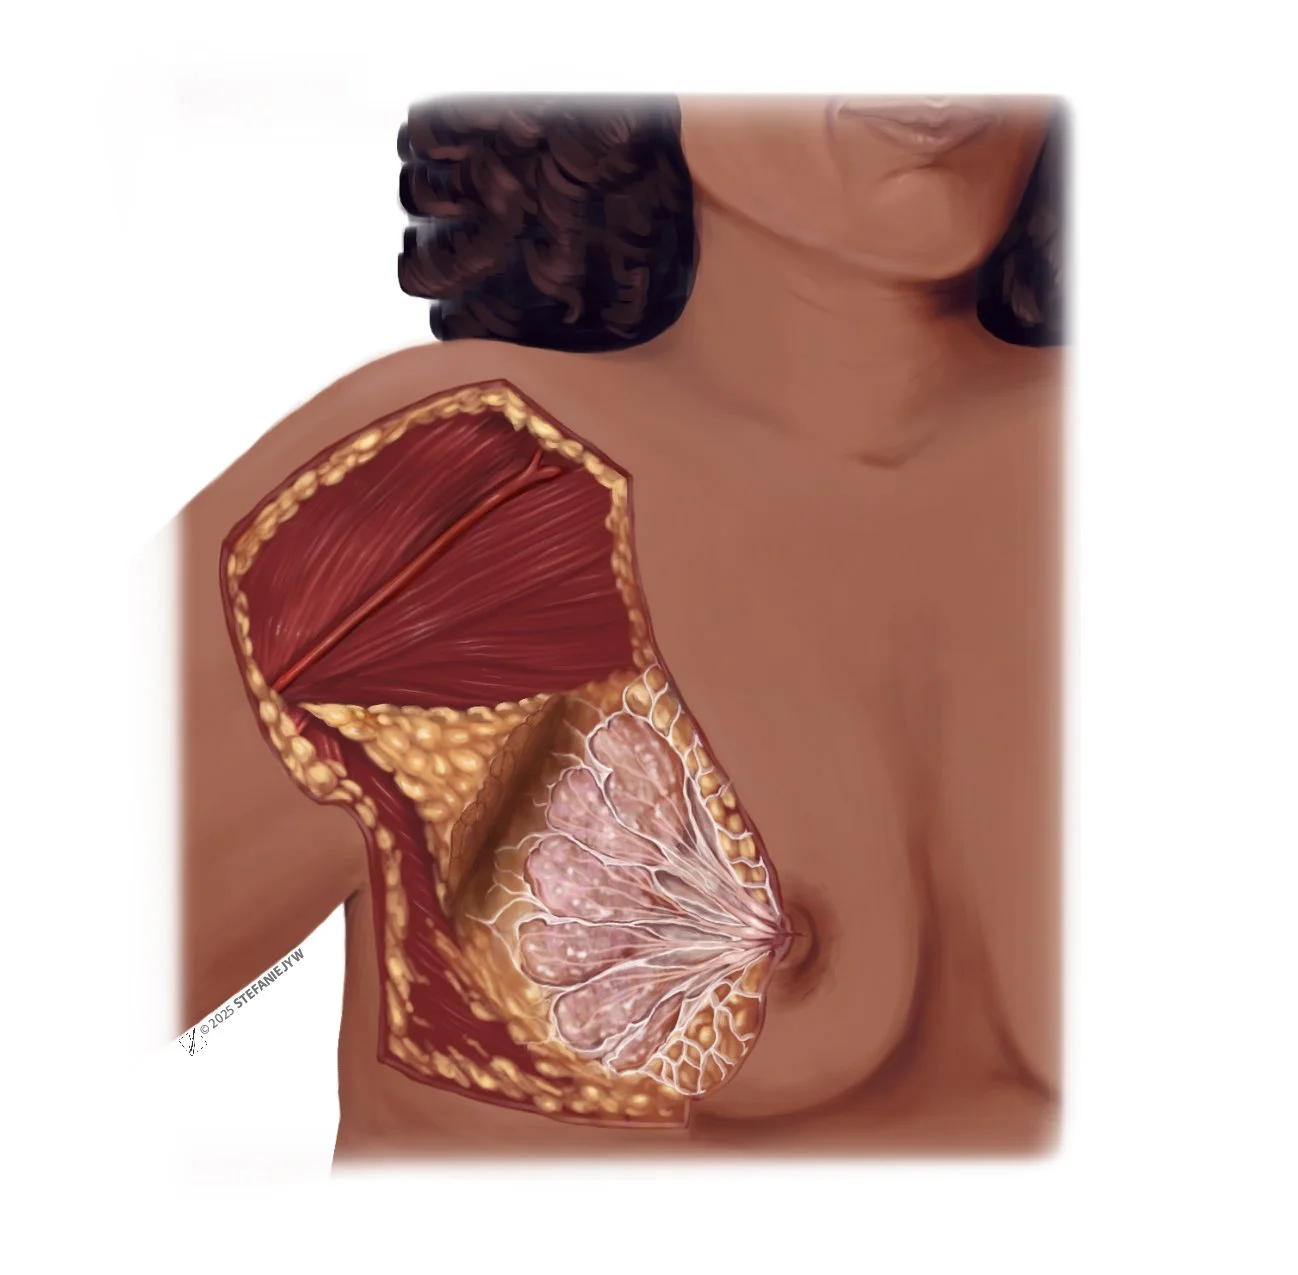

Series: Inclusive Anatomy